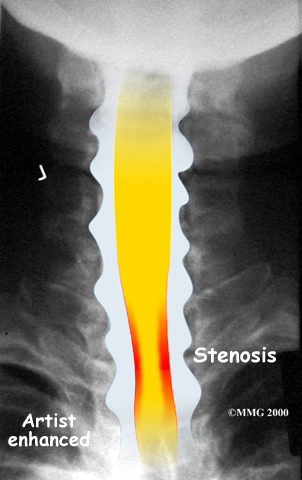

The spinal cord is a column of nerve tissue protected by a bony tube in the spinal column. Conditions that narrow the space in this tube put the spinal cord at risk of getting squeezed. This narrowing is called stenosis. When the narrowing occurs in the spinal column of the neck it is called cervical spinal stenosis, or cervical stenosis. Pressure against the spinal cord as a result of spinal stenosis causes injury to the spinal cord, which is termed myelopathy. Myelopathy is a condition that demands medical attention as it can cause serious problems including problems with the bowels and bladder, changes in the way you walk, and can affect your ability to use your fingers and hands.

The bony spinal canal normally has more than enough room for the spinal cord. Typically, the canal is just less than ¾ of an inch, or 17-18 millimeters around, which is less than the size of a small bottle cap. Spinal stenosis occurs when the canal narrows to around half an inch, or 13 millimeters or less. When the size drops even further, severe symptoms of myelopathy occur. The symptoms of myelopathy result from the actual pressure against the spinal cord itself as well as the reduced blood supply in the spinal cord as a result of the pressure.

Degeneration is the most common cause of spinal stenosis. Wear and tear on the spine from normal aging and from repeated stress and strain can cause many problems in the cervical spine. The intervertebral disc can begin to collapse, shrinking the space between the vertebrae. Bone spurs (small bony projections) may form that protrude into the spinal canal and reduce the space available for the spinal cord. The ligaments that hold the vertebrae together may become thicker and can also push into the spinal canal. All of these conditions narrow the spinal canal.

X-rays are used to look for the cause of pressure against the spinal cord. X-ray images can show if degeneration has caused the space between the vertebrae to collapse and may show if a bone spur is pressing against the spinal cord.

If more information is needed, a magnetic resonance imaging (MRI) scan may be ordered. The MRI machine uses magnetic waves rather than X-rays to show the soft tissues of the body. This test gives a clear picture of the spinal cord and can show where it is being squeezed. An MRI machine creates pictures that look like slices of the area your healthcare professional is interested in. This test does not require any special dye or a needle.

A computed tomography (CT) scan may also be ordered. The CT scan is a detailed X-ray that lets doctors see slices of bone tissue. The image can show if bone spurs are protruding into the spinal column and taking up space around the spinal cord.